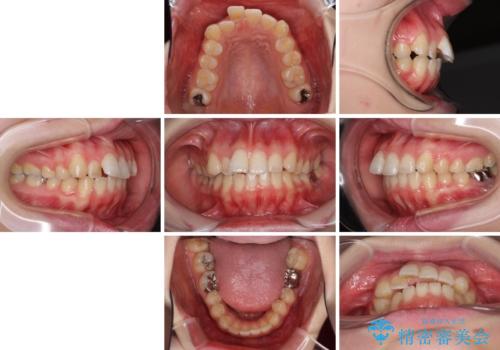

- 口の閉じにくさと割れてしまった奥歯を気にして来院された患者様です。

IPR(歯と歯の間を削る)と歯列全体の後方移動によって口元が引っ込むように設計し、インビザラインにより治療を行うこととしました。

割れてしまった奥歯は抜歯し、矯正治療中の良いタイミングでインプラントを埋入することとしました。

インプラントは、治療期間を短くすることが可能な、ストローマン社のSLActiveを使用することとしました。

上下正中がずれていたため、抜歯による矯正治療も検討しましたが、口元がそれほど突出していなかったため、非抜歯にて矯正することになりました。

その結果正中のズレは残りましたが、口を閉じたときの感覚や奥歯の咬み合わせには全く問題なく、患者様には大変満足していただきました。